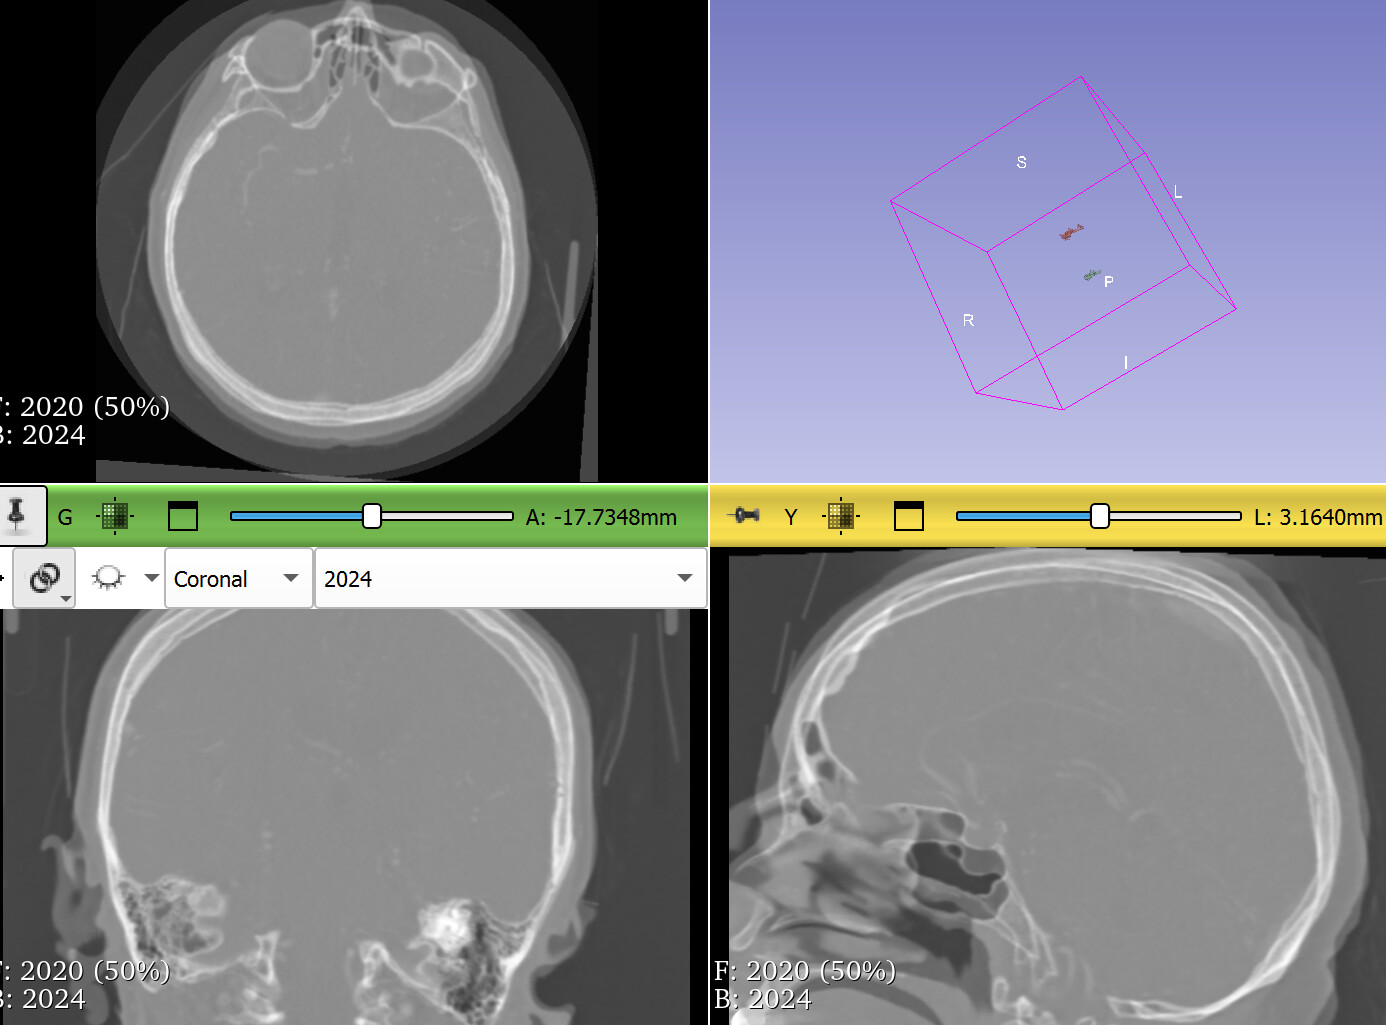

Could there be problem in sources CTs data? I attach the pre-registration pic.

Your images have several strange properties, any of them may can cause an automatic intensity-base image registration methods to struggle:

• Most registration methods generally require the images cover the same region. Your images do not meet this requirement. To fix this, probably the easiest is to crop the images to approximately to the same region.

• The image edges coincide edge of anatomy (skull touches the image edge). This is an issue because image processing methods often need to extrapolate a little bit beyond the image region and this extrapolation will fail if the intensity near the image edge is non-uniform (it is fine if the image edge cuts through the middle of tissue or cuts through the middle of air, but the image edge should not be at an anatomical region boundary).

• There is resampling artifact near the image edges. It would be better to cut them off.

• Image intensity range is off. Most medical images are in the range of +/- few thousand, while yours are in few ten thousands. This may result in default registration presets not working ideally on the images.